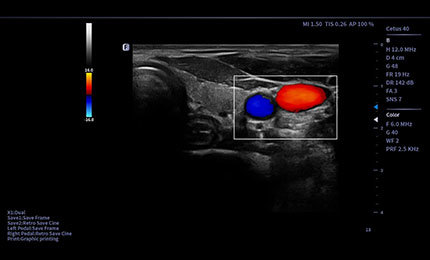

Elastografia w czasie rzeczywistym to nowa nieinwazyjna i bezbolesna technika, która pomaga określić twardość organów oraz innych struktur takich jak piersi czy tarczyca. Obrazowanie elastyczne dostarcza użytkownikom dynamicznych informacji wizualnych i pokazuje sztywność organów, co jest pomocne w bezpośredniej i ilościowej diagnozie oraz leczeniu.